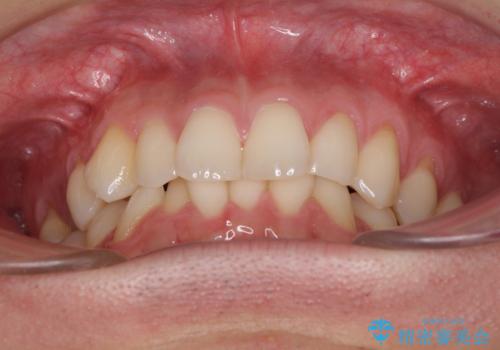

ディープバイトと叢生 インビザラインによる矯正治療

- 前歯のディープバイトと叢生を気にして来院された患者様です。

目立ちにくい装置を希望されていたため、ワイヤー装置とインビザラインを提案したところ、インビザラインを希望されました。

上下ともに叢生が認められたため、親知らずすべてを抜歯し、歯列全体を後方へ移動させることで歯列を整えることとしました。

ディープバイトもデコボコも改善され、気になっていた銀歯もセラミックとなり、患者様には大変満足していただきました。